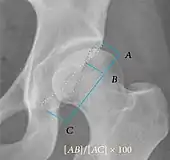

Projectional radiography ("X-ray")is often considered first line for FAI.[10] Anterior-posterior pelvis and a lateral image of the hip in question should be attained.[10] A 45-degree Dunn view is also recommended.[10][19]

| Femoral head-neck offset | ![]() |

Offset of the femoral head with regard to most prominent aspect of the femora neck | >10 mm |

| Offset percentage | Femoral head-neck offset related to femoral head diameter | >0.18

| |